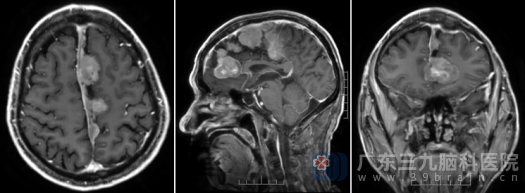

入院后,医生为王先生安排了更精细的术前头颅MR检查,结果清晰地显示:大脑镰旁左侧为主、上矢状窦旁、双侧额部大脑镰旁有多发占位性病变,考虑脑膜瘤可能性大。 这意味着,王先生的颅内并非只有一个肿瘤,而是多个肿瘤同时存在,分布在重要的脑功能区附近,手术难度和风险陡然增加。